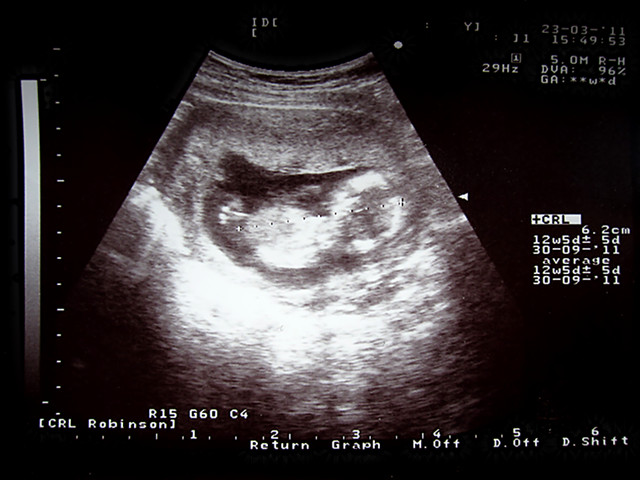

3.23 第三次B超

Shely长大很多了

12周+5天 身高6.2CM

医生说听胎心像是女生 但要16周后才能确定